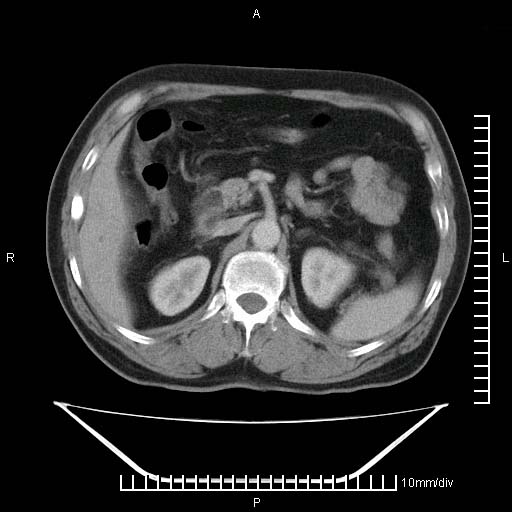

标题: CT25082:肝脏增强:男性,70岁 [打印本页]

标题: CT25082:肝脏增强:男性,70岁

患者以心脏疾病收住院,腹部无明显症状,b超查肝脏有占位。

肝内多发转移瘤,右下肺炎症并少量胸水。胃壁增厚建议胃镜,胰尾部“病变”为肠管。

1)肝脏多发性转移瘤(不排除胰尾癌转移所致可能)。2)腹水。3)右侧少量胸腔积液。

ct25082 结果:转移瘤

外院mr结果:胰尾恶性占位。